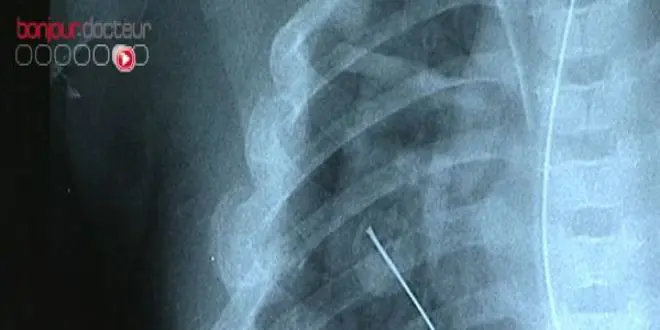

Jusqu'au 6 janvier 2013, le Musée des arts et métiers de Paris, propose une exposition retraçant l'histoire de l'imagerie biomédicale en partenariat avec le CNRS. "La vie en transparence" invite le visiteur à découvrir les différentes techniques et application de l'imagerie, ainsi que les avancées qu'elle a permises.

En plus des galeries d'images et des différents films en deux et trois dimensions montrant les avancées des techniques d'imagerie, l'exposition met à disposition du public des dispositifs interactifs, dont un échographe, afin de permettre à chacun d'explorer son propre corps.

Trois espaces et de nombreux ateliers grâce auxquels l'IRM, les radios et les scanners n'auront plus de secrets pour vous. Il est d'ailleurs possible de tester ses nouvelles connaissances à la fin de la visite à l'aide d'un quizz.